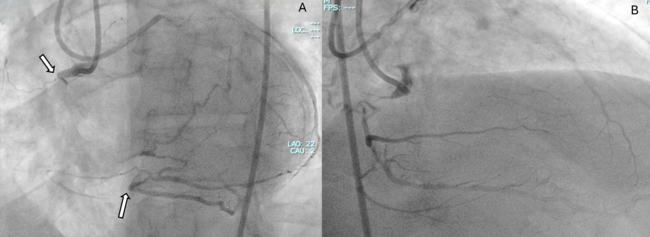

Video 5. Balloon via retrograde epicardial inflated and set for the Controlled Antegrade and Retrograde Tracking (CART) technique.